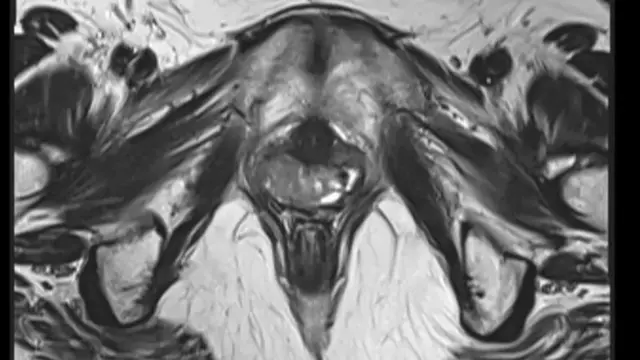

ایک برس بعد جب وہ 17 برس کی ہوئیں تب اُنھوں نے خون کے ٹیسٹ، الٹراساؤنڈ اور دیگر گائیناکولوجیکل ٹیسٹ کروائے۔ اُس وقت ڈاکٹر یہ دیکھ کر حیران رہ گئے کہ ان میں رحمِ مادر تھا اور نہ ہی اندام نہانی کی نالی۔

برازیل کی فیڈرل یونیورسٹی آف ساؤ پاؤلو میں جنسی اعضا کے نقائص کے کلینک کی کوآرڈینیٹر کلاڈیا ٹکانو کہتی ہیں کہ ’ہم پیڑو کی ہڈی کا ٹیسٹ، الٹراساؤنڈ اور ایک جینیاتی ٹیسٹ کر سکتے ہیں تاکہ یہ دیکھیں کہ مریض میں XX کروموسومز ہیں یا نہیں۔‘